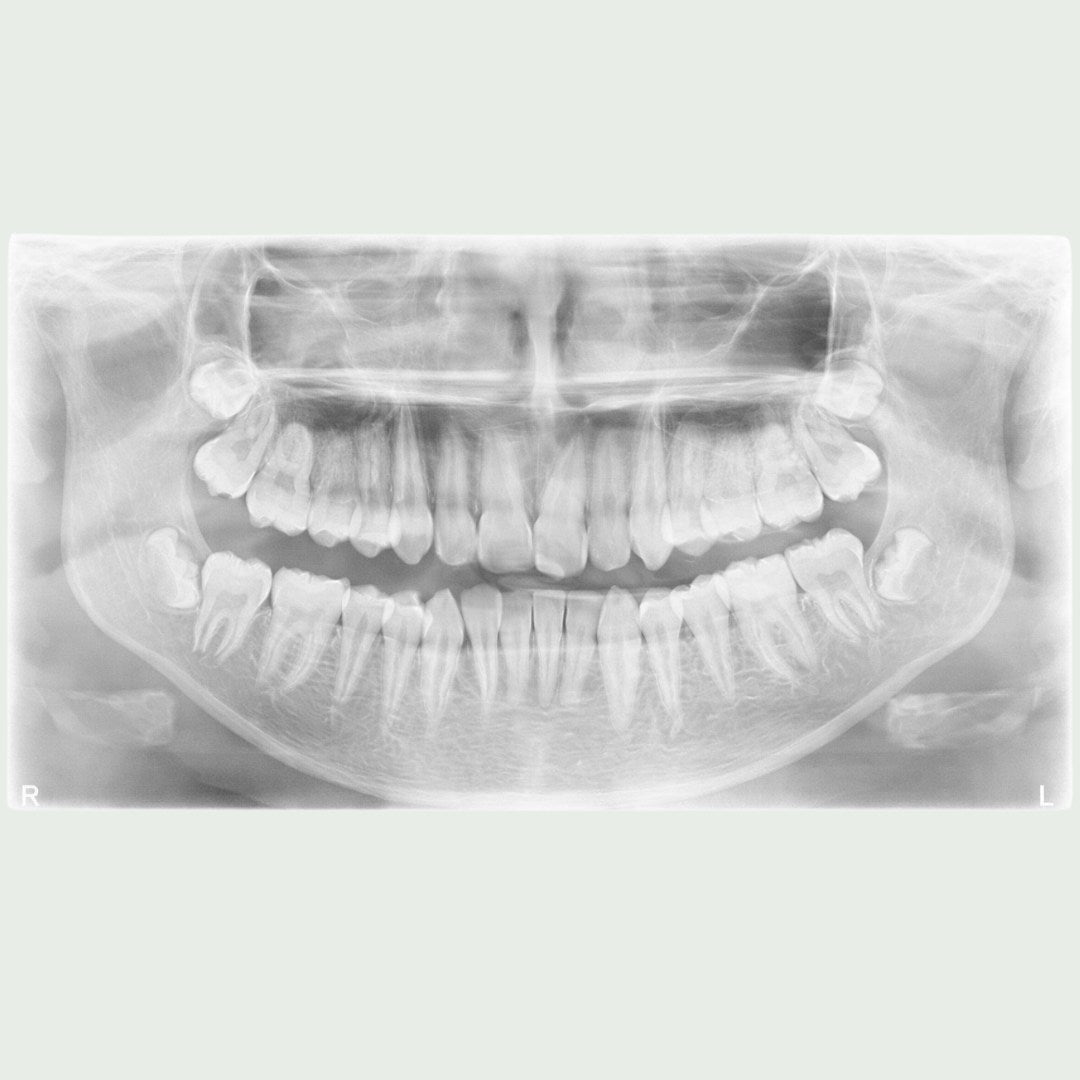

Røntgenbilder er et viktig diagnostisk verktøy i moderne tannhelse. Hos Clinica MedSpa benytter vi avansert røntgenteknologi for å få detaljerte bilder av tennene, kjeven og omkringliggende strukturer. Dette gjør det mulig for tannlegen å oppdage skjulte problemer som ikke kan sees med det blotte øye, som karies i tennene, infeksjoner under tannkjøttet, eller problemer med kjeven. Røntgenbilder gir oss en grundig innsikt i tannhelsen din, som kan bidra til tidlig påvisning av problemer og mer presis behandling.

Vi benytter digitale røntgenbilder, som gir høy oppløsning og umiddelbare resultater, samtidig som det er mer skånsomt for pasientens helse sammenlignet med tradisjonelle røntgenmetoder.

Digitale røntgenbilder er essensielt for presis diagnostikk og effektiv behandling. Vi bruker moderne røntgenteknologi som gir svært detaljerte bilder av tenner, tannrøtter, kjeveben og omliggende strukturer. Dette gjør at tannlegen raskt og nøyaktig kan identifisere problemer som karies, betennelser, infeksjoner og andre skjulte tilstander.